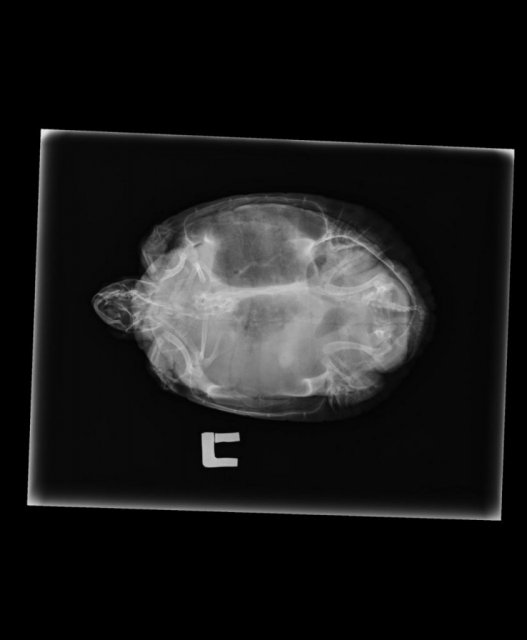

Характерное потемнение в правой части туловища на рентгеновском снимке

Около 2 месяцев назад на панцире появилось что-то вроде затертости/царапины на панцире. Подумали, что проблема в недостатке кальция, либо, возможно он упал с суши/поцарапался, ничего не подозревая свозили на рентген, чтобы предупредить различные другие проблемы. Снимок показал это. Вряд-ли пневмония, условия для неё не подходящие, да и признаков болезни черепаха не выказывала. Чувствует себя чепик нормально, от еды не отказывается, в воде плавает, на суше тоже сидит. Ветеринар сказал, что внутри нечто больше похожее на воздух, чем на жидкость и находится оно не в лёгких. Подскажите, пожалуйста, в чем проблема, как лечить, связано ли это с царапиной на панцире?

в такой проекции невозможно узнать есть пневмония или нет, тут не видно самих лёгких за внутренними органами. Легкие смотрят в других проекциях, номер 2 и 3

у черепахи деформация скорее генетического характера, т.к. сильно искривлён позвоночник. И скорее всего объём лёгких тоже искажен этой аномалией.

Т.е. если Вы хотите точно понять что это за чёрное пятно - нужно сделать ещё две или хотя бы одну проекцию 2 или 3.

Я бы сказала, что тут смещение внутренних органов из-за искривления панциря, поэтому так выглядит.